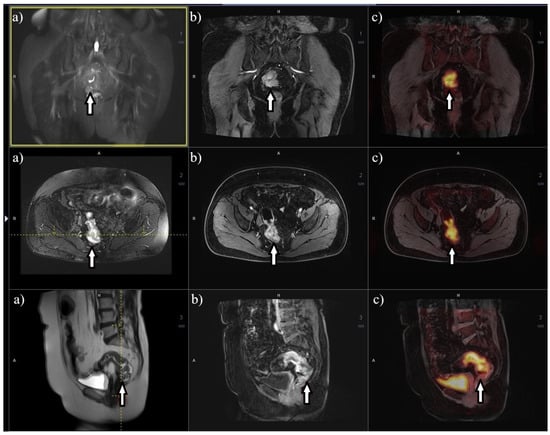

8. Metabolic Imaging 18F-FDG PET/MRI

- Rutegård, M.K.; Båtsman, M.; Axelsson, J.; Brynolfsson, P.; Brännström, F.; Rutegård, J.; Ljuslinder, I.; Blomqvist, L.; Palmqvist, R.; Rutegård, M.; et al. PET/MRI and PET/CT hybrid imaging of rectal cancer–description and initial observations from the RECTOPET (REctal Cancer trial on PET/MRI/CT) study. Cancer Imaging 2019, 19, 52. [Google Scholar] [CrossRef] [PubMed]

- Crimì, F.; Valeggia, S.; Baffoni, L.; Stramare, R.; Lacognata, C.; Spolverato, G.; Albertoni, L.; Spimpolo, A.; Evangelista, L.; Zucchetta, P.; et al. [18F]FDG PET/MRI in rectal cancer. Ann. Nucl. Med. 2021, 35, 281. [Google Scholar] [CrossRef]